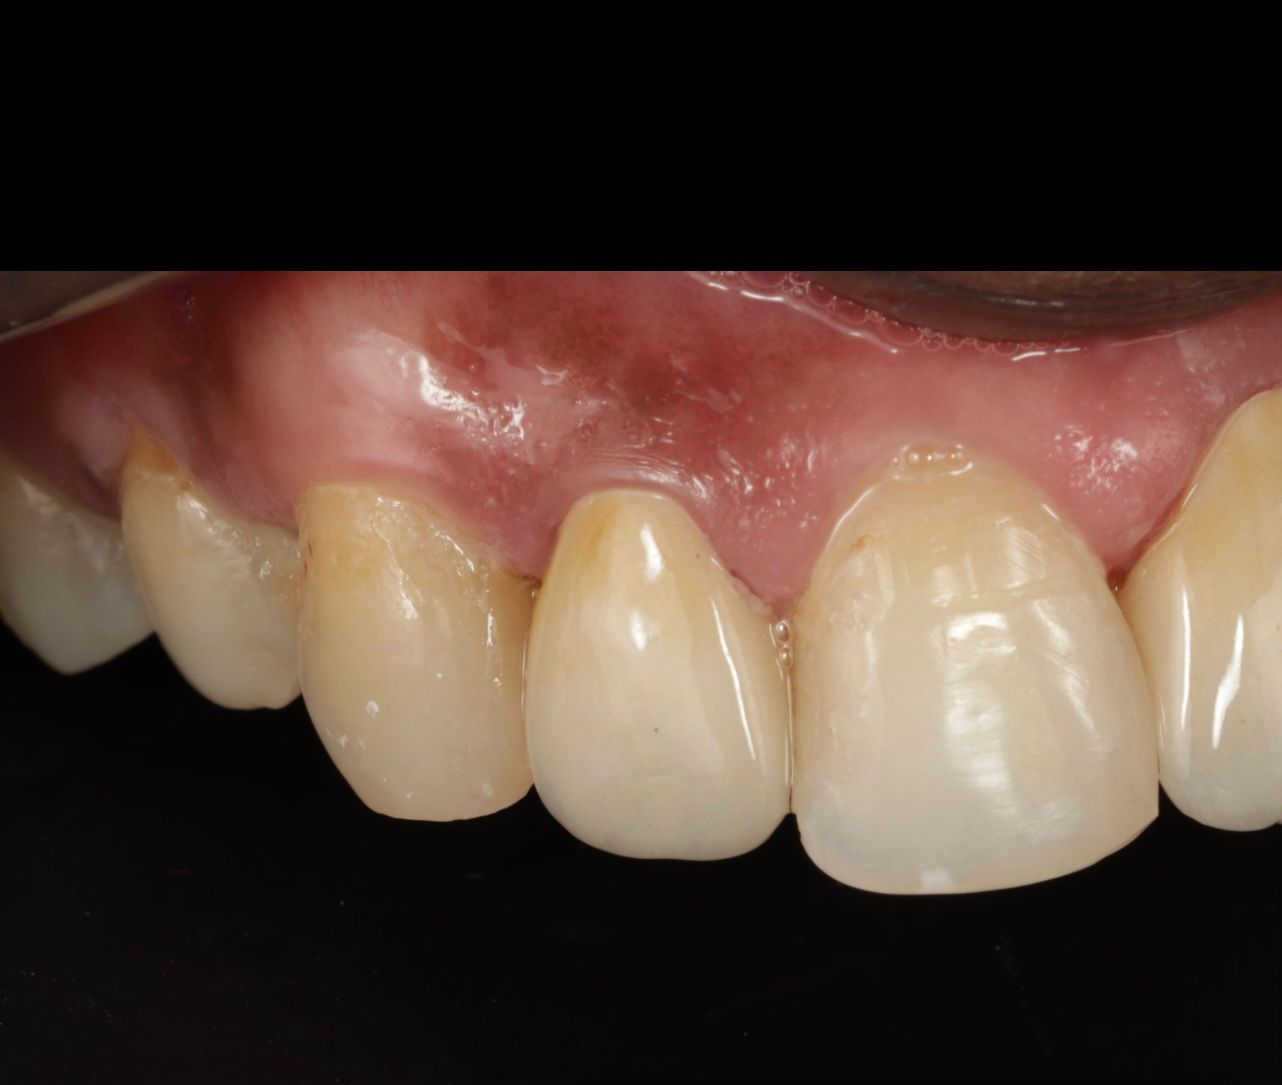

Clinical Outcome

This case demonstrates how a previously treated crowned tooth with chronic infection can be successfully saved through advanced retreatment, disinfection, and restorative protocols. The tooth was preserved in function and beauty — a testament to Apollo Hospitals Jabalpur’s excellence in endodontic care under Dr. Samay P. Chavan.